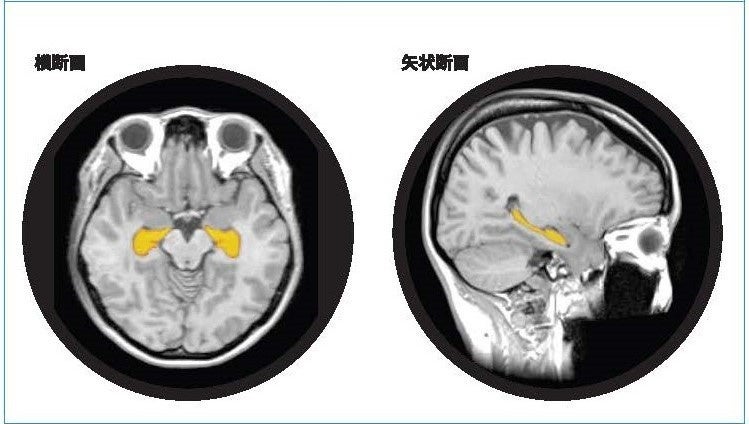

「BrainSuite®」は、脳MRI画像のAI解析技術等を利用することで海馬の体積や萎縮程度を測定・評価し、同性・同世代と比較した脳の健康状態を可視化します。受検者にはBrainSuite®専用会員ページ「MyPage」が用意され、脳の健康維持・改善方法についてアドバイスを提供します。20代から80代の幅広い年齢層を対象に、「生涯健康脳」の実現を最新の脳医学の観点からサポートする検査サービスです。

アルツハイマー型認知症は、顕著な脳萎縮を特徴としおり、脳の中でも海馬の萎縮は、20・30代から始まり、生活習慣要因によっては加齢性変化以上に萎縮が加速します。予防として健康なうちより生活習慣の改善をスタートすることがとても大切です。